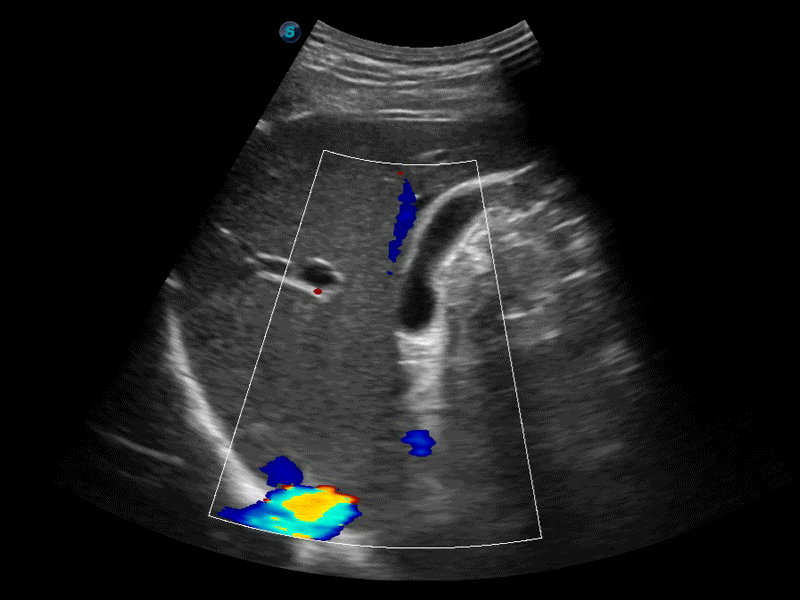

凸陣、線陣和相控陣探頭進(jìn)行實時掃描時,開啟擴(kuò)展成像模式,可以擴(kuò)展超聲圖像視野,以便更完整地查看大的病灶或組織器官的解剖結(jié)構(gòu)。

通過色彩血流和實時寬景相結(jié)合,可觀察到完整的靜脈或動脈的血流,方便醫(yī)生檢查。實時掃查過程中,如有任何操作失誤也可以很容易地進(jìn)行回掃擦除,而不會中斷掃查。